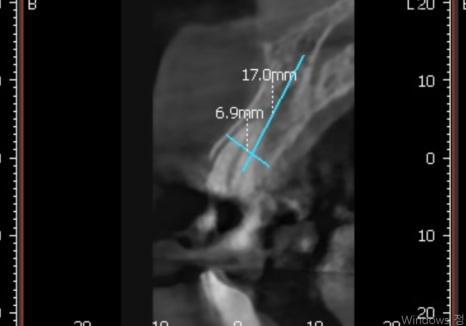

뿌리만 남은 앞니는 우선 발치를 진행했는데,

다행히 CT 상 잇몸뼈가 아주 튼튼한 상태였어요.

240628

덕분에 번거로운 뼈이식 과정 없이

그날 바로 임플란트를 심어드리는

즉시 식립이 가능했습니다.

그렇게 두 달 정도 시간이 흘러

임플란트와 뼈가 단단하게 잘 붙은 것을 확인하고,